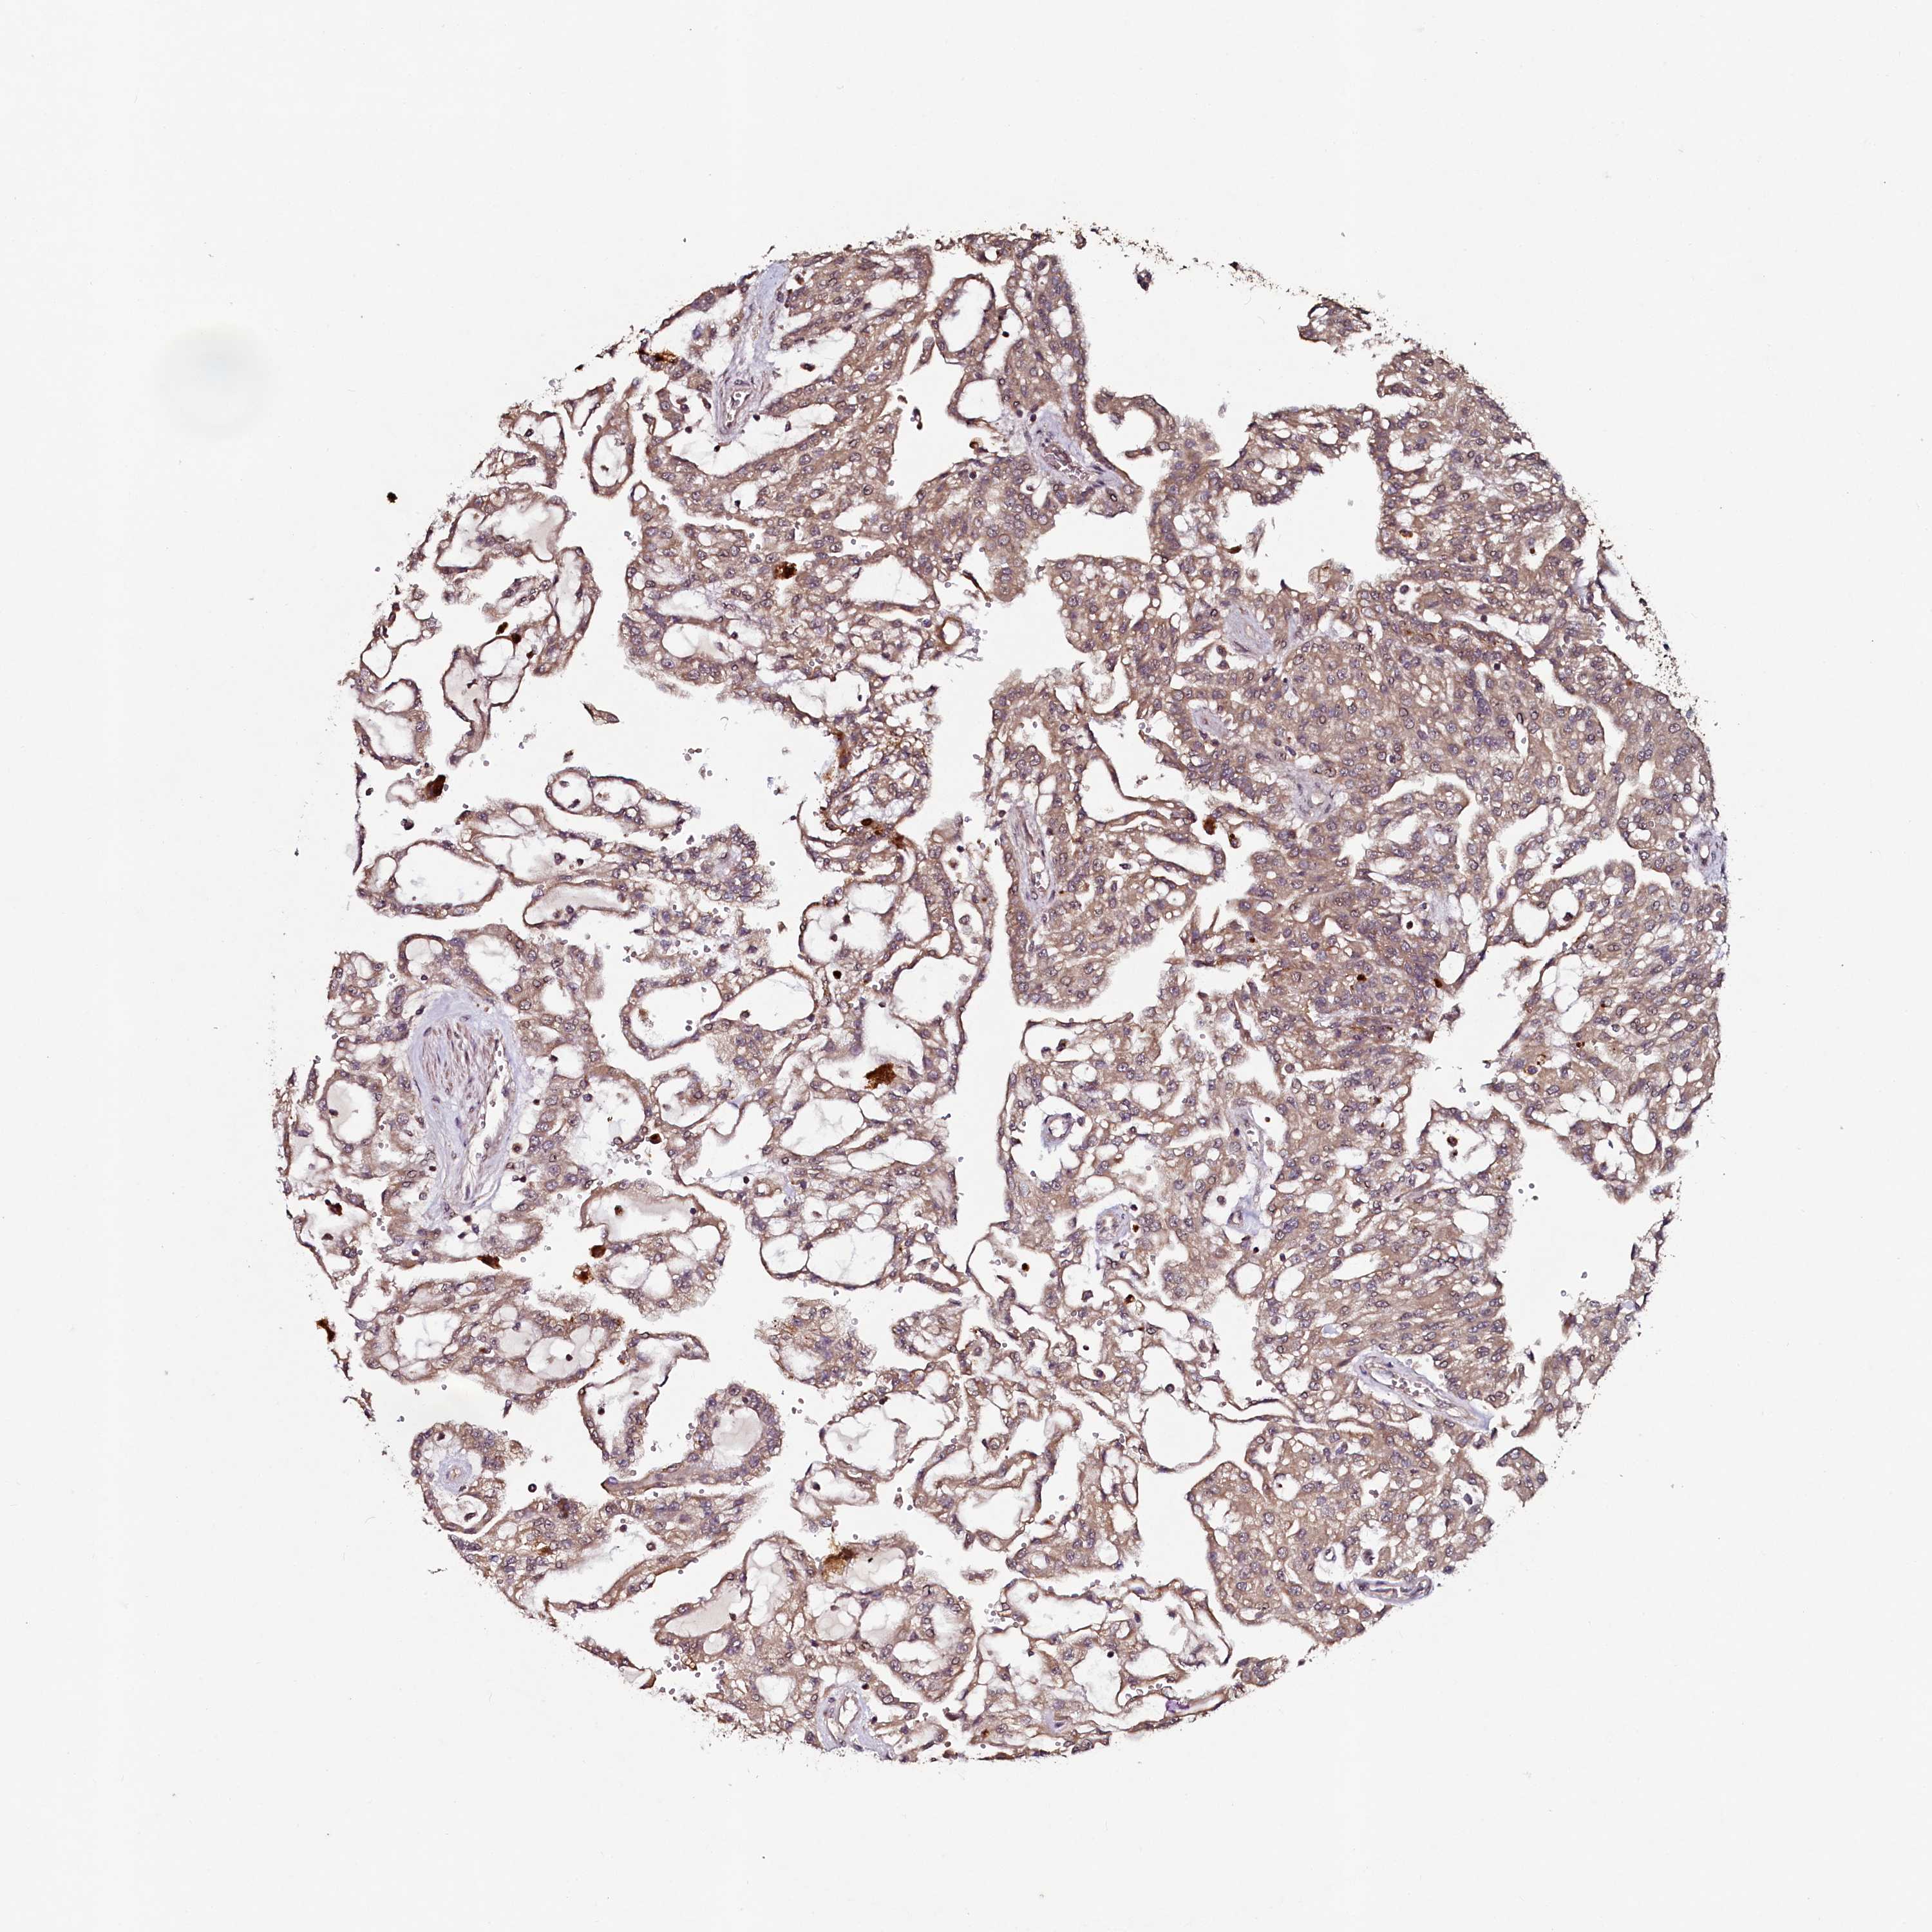

KIDNEY RENAL CLEAR CELL CARCINOMA (TCGA) - Interactive survival scatter ploti

The Survival Scatter plot shows the clinical status (i.e. dead or alive) for all individuals in the patient cohort, based on the same data that underlies the corresponding Kaplan-Meier plots. Patients that are alive at last time for follow-up are shown in blue and patients who have died during the study are shown in red.

The x-axis shows the expression levels (FPKM) of the investigated gene in the tumor tissue at the time of diagnosis. The y-axis shows the follow-up time after diagnosis (years). Both axes are complimented with kernel density curves demonstrating the data density over the axes. The top density plot shows the expression levels (FPKM) distribution among dead (red) and alive patients (blue). The right density plot shows the data density of the survived years of dead patients with high and low expression levels respectively, stratified using the cutoff indicated by the vertical dashed line through the Survival Scatter plot. This cutoff is automatically defined based on the FPKM cutoff that minimizes the p-score. The cutoff can be changed by dragging the vertical line or by entering a cutoff value in the square labeled "Current cut-off".

Under the Survival Scatter plot the p-score landscape (black curve; left axis) is shown together with dead median separation (red curve; right axis). Dead median separation is the difference in median mRNA expression between patients who have died with high and low expression, respectively. It is calculated as follows: median FPKM expression of dead patients with high expression - median FPKM expression of dead patients with low expression. This is intended to aid the user in visually exploring custom cutoffs and the associated p-scores and dead median separation.

Individual patient data is displayed and can be filtered by clicking on one or more of the category buttons on the top of the page. Categories describing expression level and patient information include: high, low, alive, dead, female, male and tumor stages. The scale of the x-axis can be toggled between linear and log-scale by clicking on the "x log" button. Mouse-over function shows TCGA ID, patient information and mRNA expression (FPKM) for each patient.

& Survival analysisi

Kaplan-Meier plots summarize results from analysis of correlation between mRNA expression level and patient survival. Patients were divided based on level of expression into one of the two groups "low" (under cut off) or "high" (over cut off). X-axis shows time for survival (years) and y-axis shows the probability of survival, where 1.0 corresponds to 100 percent.

SEC24C is potential prognostic, high expression is favorable in Kidney Renal Clear Cell Carcinoma (TCGA)

Best expression cut offi

Based on the FPKM value of each gene, patients were classified into two groups and association between prognosis (survival) and gene expression (FPKM) was examined. The best expression cut-off refers the FPKM value that yields maximal difference with regard to survival between the two groups at the lowest log-rank P-value. Best expression cut-off was selected based on survival analysis .

When clicking on this number, the vertical dashed line indicating cut-off, the interactive survival plot, and the Kaplan-Meier curve will be adjusted to show results based on the best expression cut-off.

: 29.79

TCGA RNA samplesi

RNA-seq data is reported as average FPKM (number Fragments Per Kilobase of exon per Million reads), generated by the The Cancer Genome Atlas (TCGA) .

Normal distribution across the dataset is visualized with box plots, shown as median and 25th and 75th percentiles. Points are displayed as outliers if they are above or below 1.5 times the interquartile range. FPKM values of the individual samples are presented next to the box plot.

Average pTPM 33.7

Number of samples 521